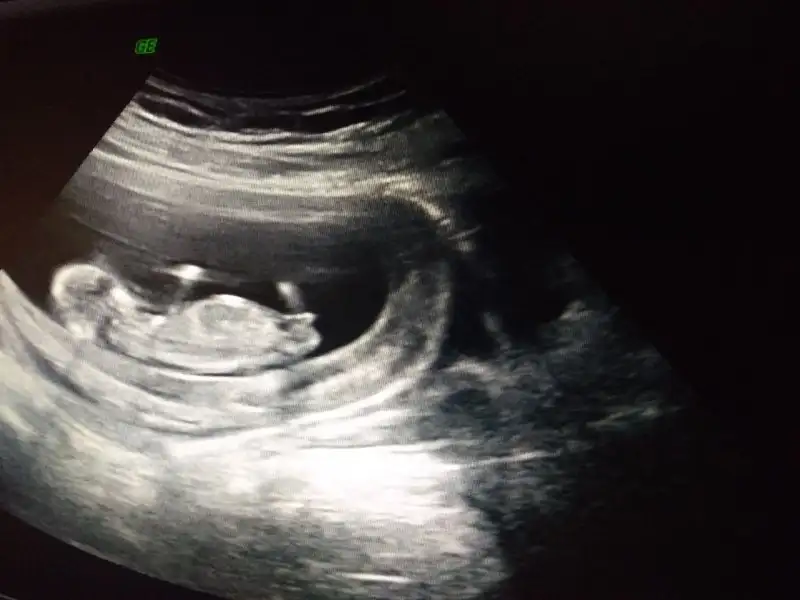

Güzel haberlerle dönersin umarım canım bizi de bilgilendirGünaydın annişler doktora geldik dua edin hersey yolunda olsunçok heyecanlıyız

Günaydın annişler doktora geldik dua edin hersey yolunda olsunçok heyecanlıyız

Kiza benziyor

Bana 13+0 da %80 erkek dedi ama cok kaptirmak istemiyorum13 haftalık anneler cinsiyet öğrenebildiniz mi

Canım Inşallah her şey yolundadır benim de 13.00 dan sonra kontrolüm varmış inşallah bende de her şey yolundadırGünaydın annişler doktora geldik dua edin hersey yolunda olsunçok heyecanlıyız